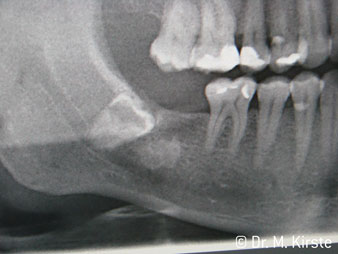

Die professionelle Lagergestaltung im Innenleben des Handstückkopfes garantiert einen ruhigen Lauf der Bohrer, bei der Zahn- oder Wurzelseparation (Abb. 4 - 9) zeigt sich ein beeindruckendes Schnittbild ohne Schlageffekte.

Abb. 4

Abb. 6

Abb. 8